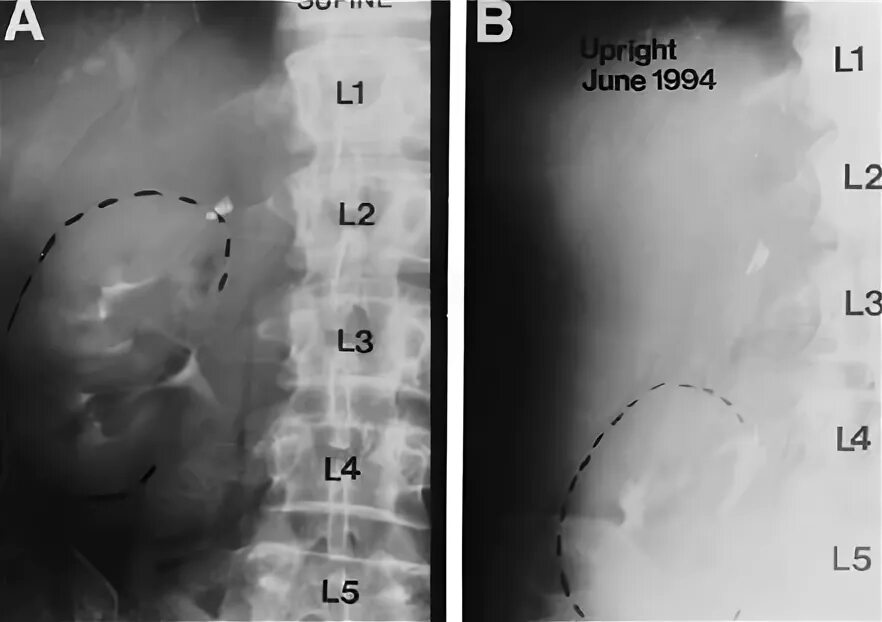

Опущение почки симптомы и последствия